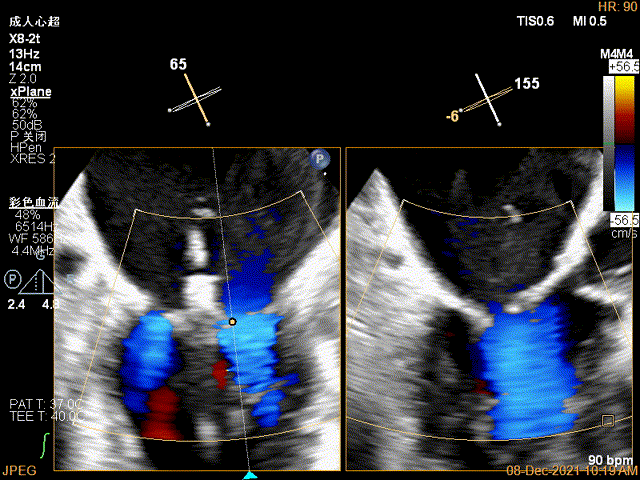

X-plane:下夹子尝试先捕获2区瓣叶

夹子关闭过程中,Color提示2区反流逐渐减少,残余反流位于夹子外侧

x-plane验证前后叶抓捕后bond明显

1、此患者打破了风湿性心脏瓣膜患者不能做TEER治疗的传统观念,在经胸超声心动图的报告上风湿性心脏瓣膜病,二尖瓣瓣叶增厚,瓣口狭窄的初步印象让这个虚弱的患者险些错失了经导管介入治疗的机会。因此,对于每一个二尖瓣反流的患者,对其发病机制和解剖结构都需要全面细致的评估,即使是风湿性心脏瓣膜病变,也并非TEER治疗的绝对禁忌,利用经食道超声心动图的最新优势,结合2D、3D、 multivue、血流多普勒参数等多个维度去精准评估患者的解剖特征和血流动力学状态,为TEER治疗的可行性和手术测略做出准确判断。